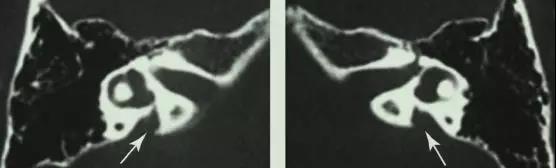

而目前高分辨率颞骨CT与内耳核磁是诊断本病的金标准。在CT上可以发现前庭导水管骨性结构的扩大(半规管总脚到前庭水管外口1/2直径大于1.5mm)。在核磁上可以看到内淋巴管和囊的扩大。